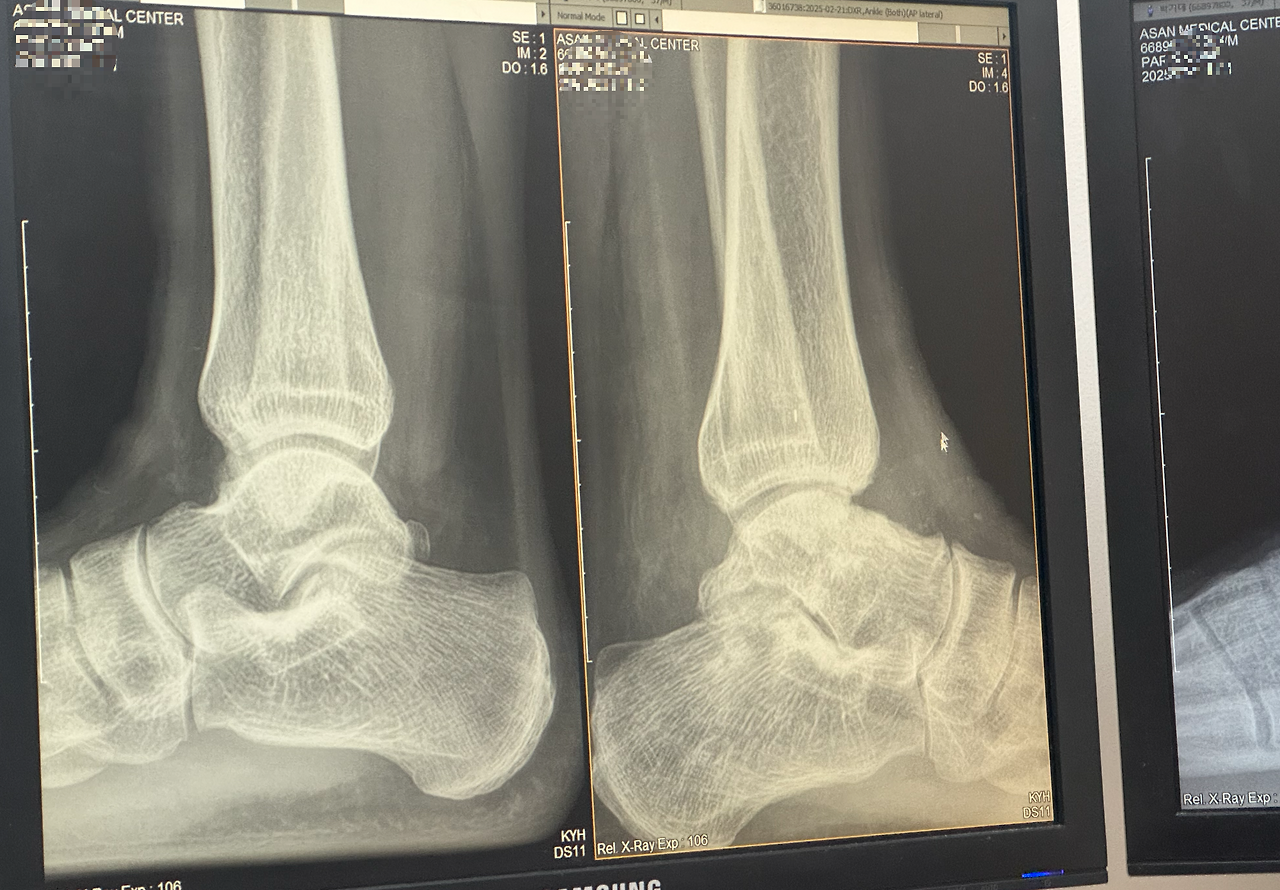

의사 선생님이 CT와 X-ray로 검진을 하자고 했다. CT와 X-ray촬영 후 다시 검진을 받았다. 의사 선생님의 소견은 이전과는 달랐다. 나는 가장 불편한 것이 발목이 수직이 아닌 상태로 굳어져 발을 딧지 않다가 딛으려고 할 때 절 수밖에 없다는 것이라고 했다. 의선생님은 그 부분은 조금씩 나아지고 있으니 좀 지켜보자고 하셨다.

거골이 완전히 매끄럽게 붙지 않아서 표면이 거칠다고 했다. 지금은 연골이 중간에 있어서 괜찮지만 조금이라도 문제가 생기면 재수술을 할 수도 있다고 하셨다. 그러고는 될 수 있으면 발을 앞으로 꺾는 운동이나 지속적으로 발 앞복으로 체중을 싣는 행동을 하지 말라고 하셨다. 아직 달리응 것이 서툴러서 연습을 하고 있었는데 이것도 중단해야 했다.